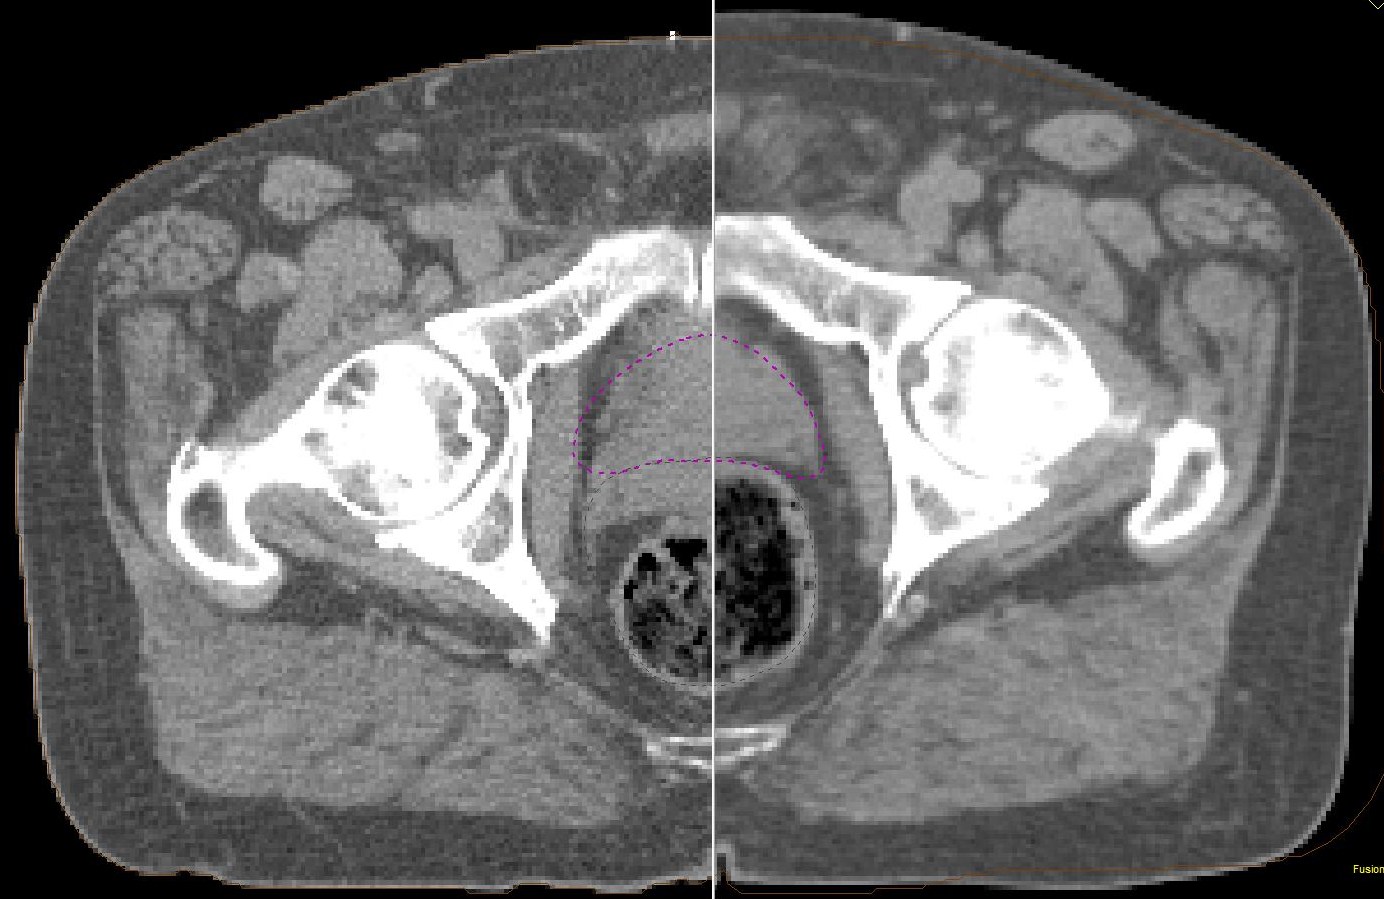

Das CT der rechten Bildhälfte wurde mit stark gefülltem Rektum gemacht. Die Wiederholung nach Darmentleerung (linke Bildhälfte) zeigt, dass das eingezeichnete ZV die dorsalen Abschnitte der Prostata nicht erfasst.